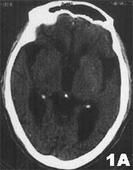

影像學表現:CT表現為斑片狀及斑點狀低密度影,MRI表現為點狀及片狀長T1WI長T2WI信號,由腦深部灰質團塊萎縮,胼胝體繼發變薄,致使腦室擴大,又由於瀰漫性髓鞘脫失而有不同程度的腦萎縮,顯示腦溝增寬,腦池擴大(如圖1~4)。有高血壓及動脈硬化的病理基礎也可發生腦出血是腔隙性梗塞的直接原因。

賓斯旺格病診斷及鑑別診斷:CT,MRI的問世,為本病的生前診斷提供了影像學依據,CT表現為雙側腦室旁白質區與半卵圓中心顯示散在性或融合性低密度區,對稱或大致對稱,基底節,內囊與丘腦區可見多發性腔隙性梗塞,重者伴腦室擴大,其室管膜面多參差不齊,呈碎布狀。MRI表現:在腦室周圍白質與半卵圓中心顯示散在或融合性病變區,T1WI呈黑色,T2WI呈白色。重度與中度顯示腦室擴大,腔隙性梗塞顯影清晰,病灶數目比CT發現的多。SAE應與多發硬化,嚴重腦積水所致的室管膜水腫,CO中毒腦水腫期,腦囊蟲病腦炎型,ALZHEIMER氏病,PICK病,及其他特異性腦白質病,這些腦白質病變根據CT,MRI的表現特點,結合臨床表現60歲以上潛隱起病,逐漸加重,若具備卒中發作,高血壓,慢性進行性痴呆三大臨床特徵,綜合分析,即可做出診斷,也可隨訪複查。